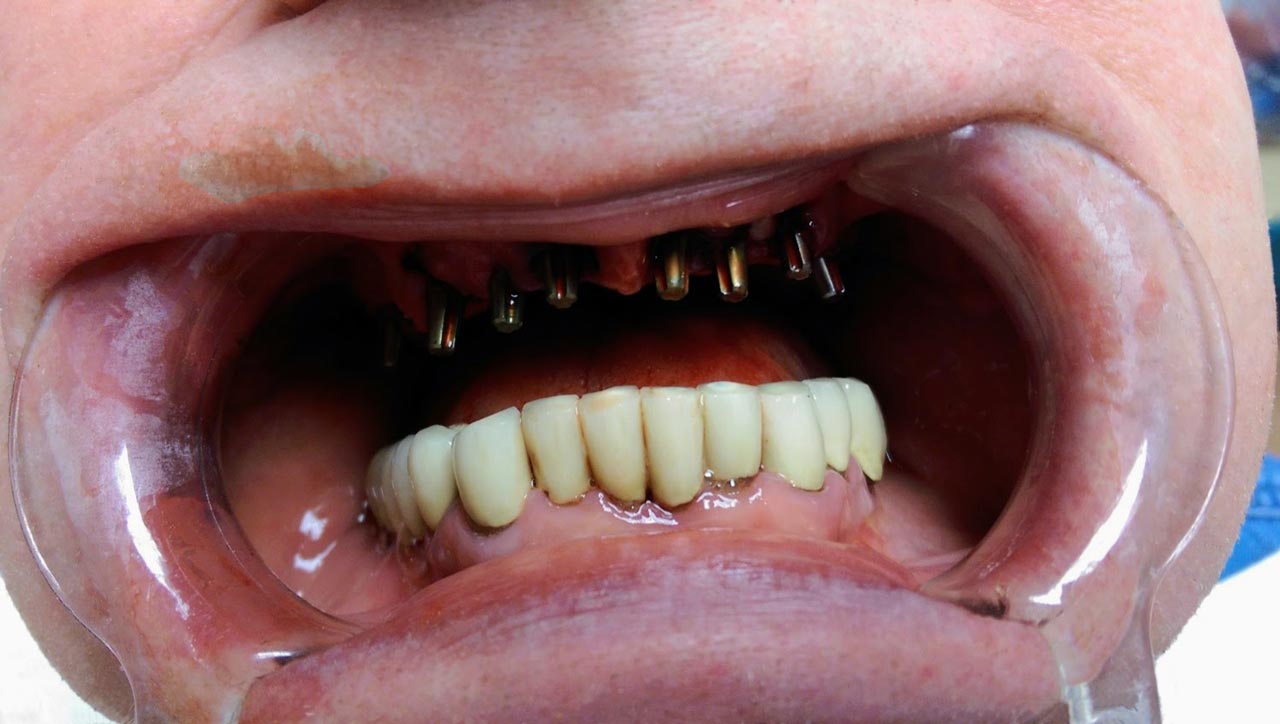

Sikerét mindenekelőtt a gyorsaságának köszönheti, hiszen a mai rohanó világban kinek van ideje, kedve fogatlanul otthon ülni heteket, hónapokat a fogpótlásra várva? Az Ihde implantációs eljárás során a páciens azonnal, de legkésőbb 72 óra múlva egy rögzített (tehát nem mozgó, nem kivehető) pótlással hagyja el a rendelőt. Ez az egyedülállóan gyors eljárás annak köszönhető, hogy azonnal tudunk implantálni szinte bárhova, akár foghúzás után is, továbbá a művelet nem jár nagy feltárásokkal, nincs szükség csontbeültetésre, így a gyógyulás folyamata is nagyon gyors és a beültetés technikájának köszönhetően maximum 72 óra múlva a korona is feltehető. Tehát ennyi idő alatt foga lesz a betegnek és az implantátum azonnal terhelhetővé is válik.

Az eljárás mellett szól az is, hogy nagyon biztonságos. A cég adatai alapján a beültetett implantátumok 98.2%-a sikeres. Az azonnali terhelésű implantátumokkal rögtön, akár foghúzás után is szinte bárhová lehet implantálni, bárkinek, legyen szó cukorbeteg, dohányos, vagy akár csontritkulásban szenvedő páciensről. Ennek köszönhető, hogy a betegek 99%-ánál alkalmazható a módszer.